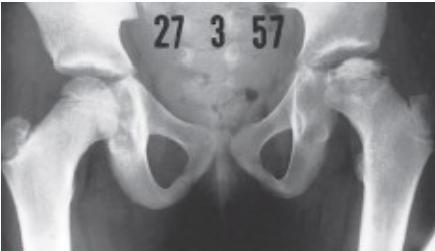

Radiographic Stages:

-

Initial/ Bone Death Stage (Sclerosis)

- May initially appear normal on x-ray

- Increased density followed by collapse

Revascularization and Repair Stage

- Reduced density and fragmentation on x-ray

Distortion and Remodeling Stage

- Distortion, flattening (coxa plana)

- Enlargement (coxa magna) with partial uncoverage

Radiological Progression:

Progression: Sclerosis → Collapse → Fragmentation → Remodeling

Imaging Examples: